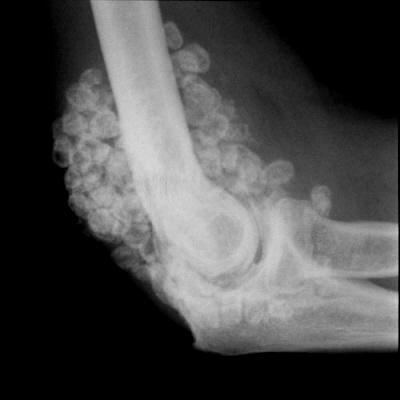

Хондроматоз – это патологическое изменение сустава, причиной которого становится перерождение синовиальной оболочки в хрящ. Это заболевание довольно редкое, может поражать любой сустав, но чаще всего страдает именно коленный сустав. Заболевание характерно для спортсменов и людей, подвергающихся регулярным тяжелым физическим нагрузкам, четкая причина возникновения неизвестна. Симптомы- боль, хруст и заклинивание сустава.

Вариант запущенного хондроматоза локтевого сусутава.

Лечение оперативное: артроскопическое удаление хондроматозных тел.